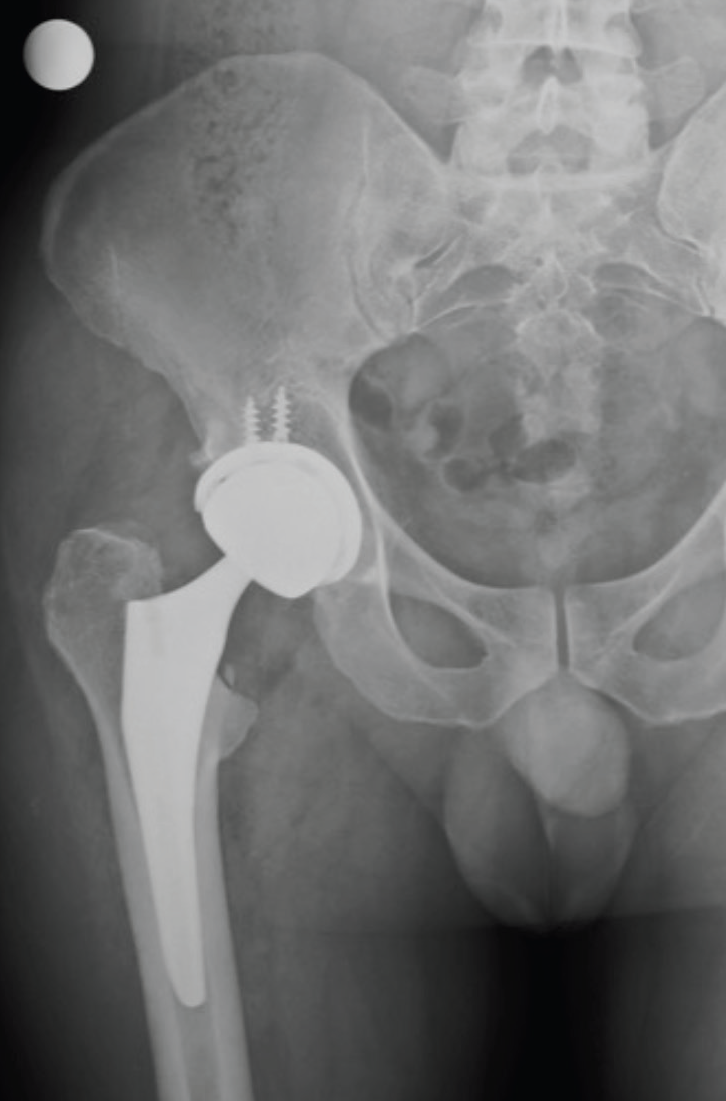

Sağ kalçasına protez uygulanan hastanın pelvis grafisi

|